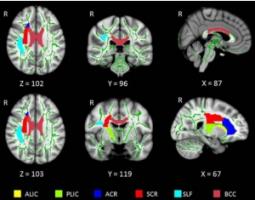

Actualité publiée il y a 4 mois 1 semaineÉPILEPSIE : Le connectome révélateur des dommages au cerveau